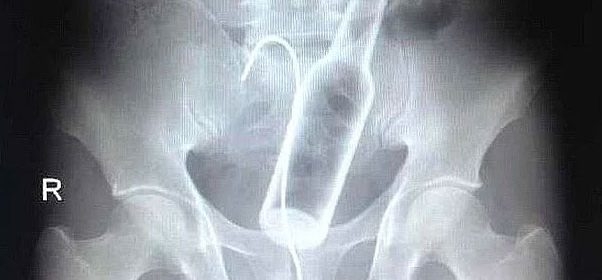

Röntgen filmlerinden çıkan akıl almaz şeyler

Hastane koridorlarına düşenler bilir… Doktora görün, tahlilleri yaptır, röntgenleri çektir falan filan derken insanın ömründen ömür gider. Gelin görün ki bu sefer çektirilen röntgenlerde öyle ilginç şeyler çıkmış ki ağzımız açık kaldı…